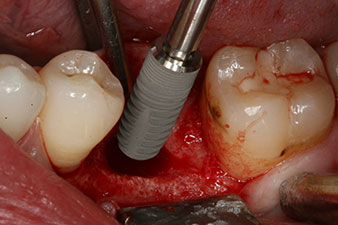

However, six weeks after the extraction incomplete ossification was found after preparation of the mucoperiosteal flap in the region of the former mesial alveolus.

The implant was placed as planned after thorough removal of the granulation tissue (blueSky, bredent).

The torque used for the machine-driven placement was 43 Ncm. In addition, after screwing a measuring post (SmartPeg) specially matched to the implant, the ISQ value was measured with the probe of the W&H Osstell ISQ module.